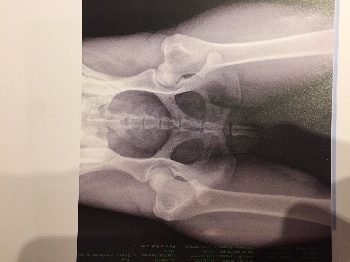

Dépistage de dysplasie : Fanfan Azul de Los Laureles

A/A